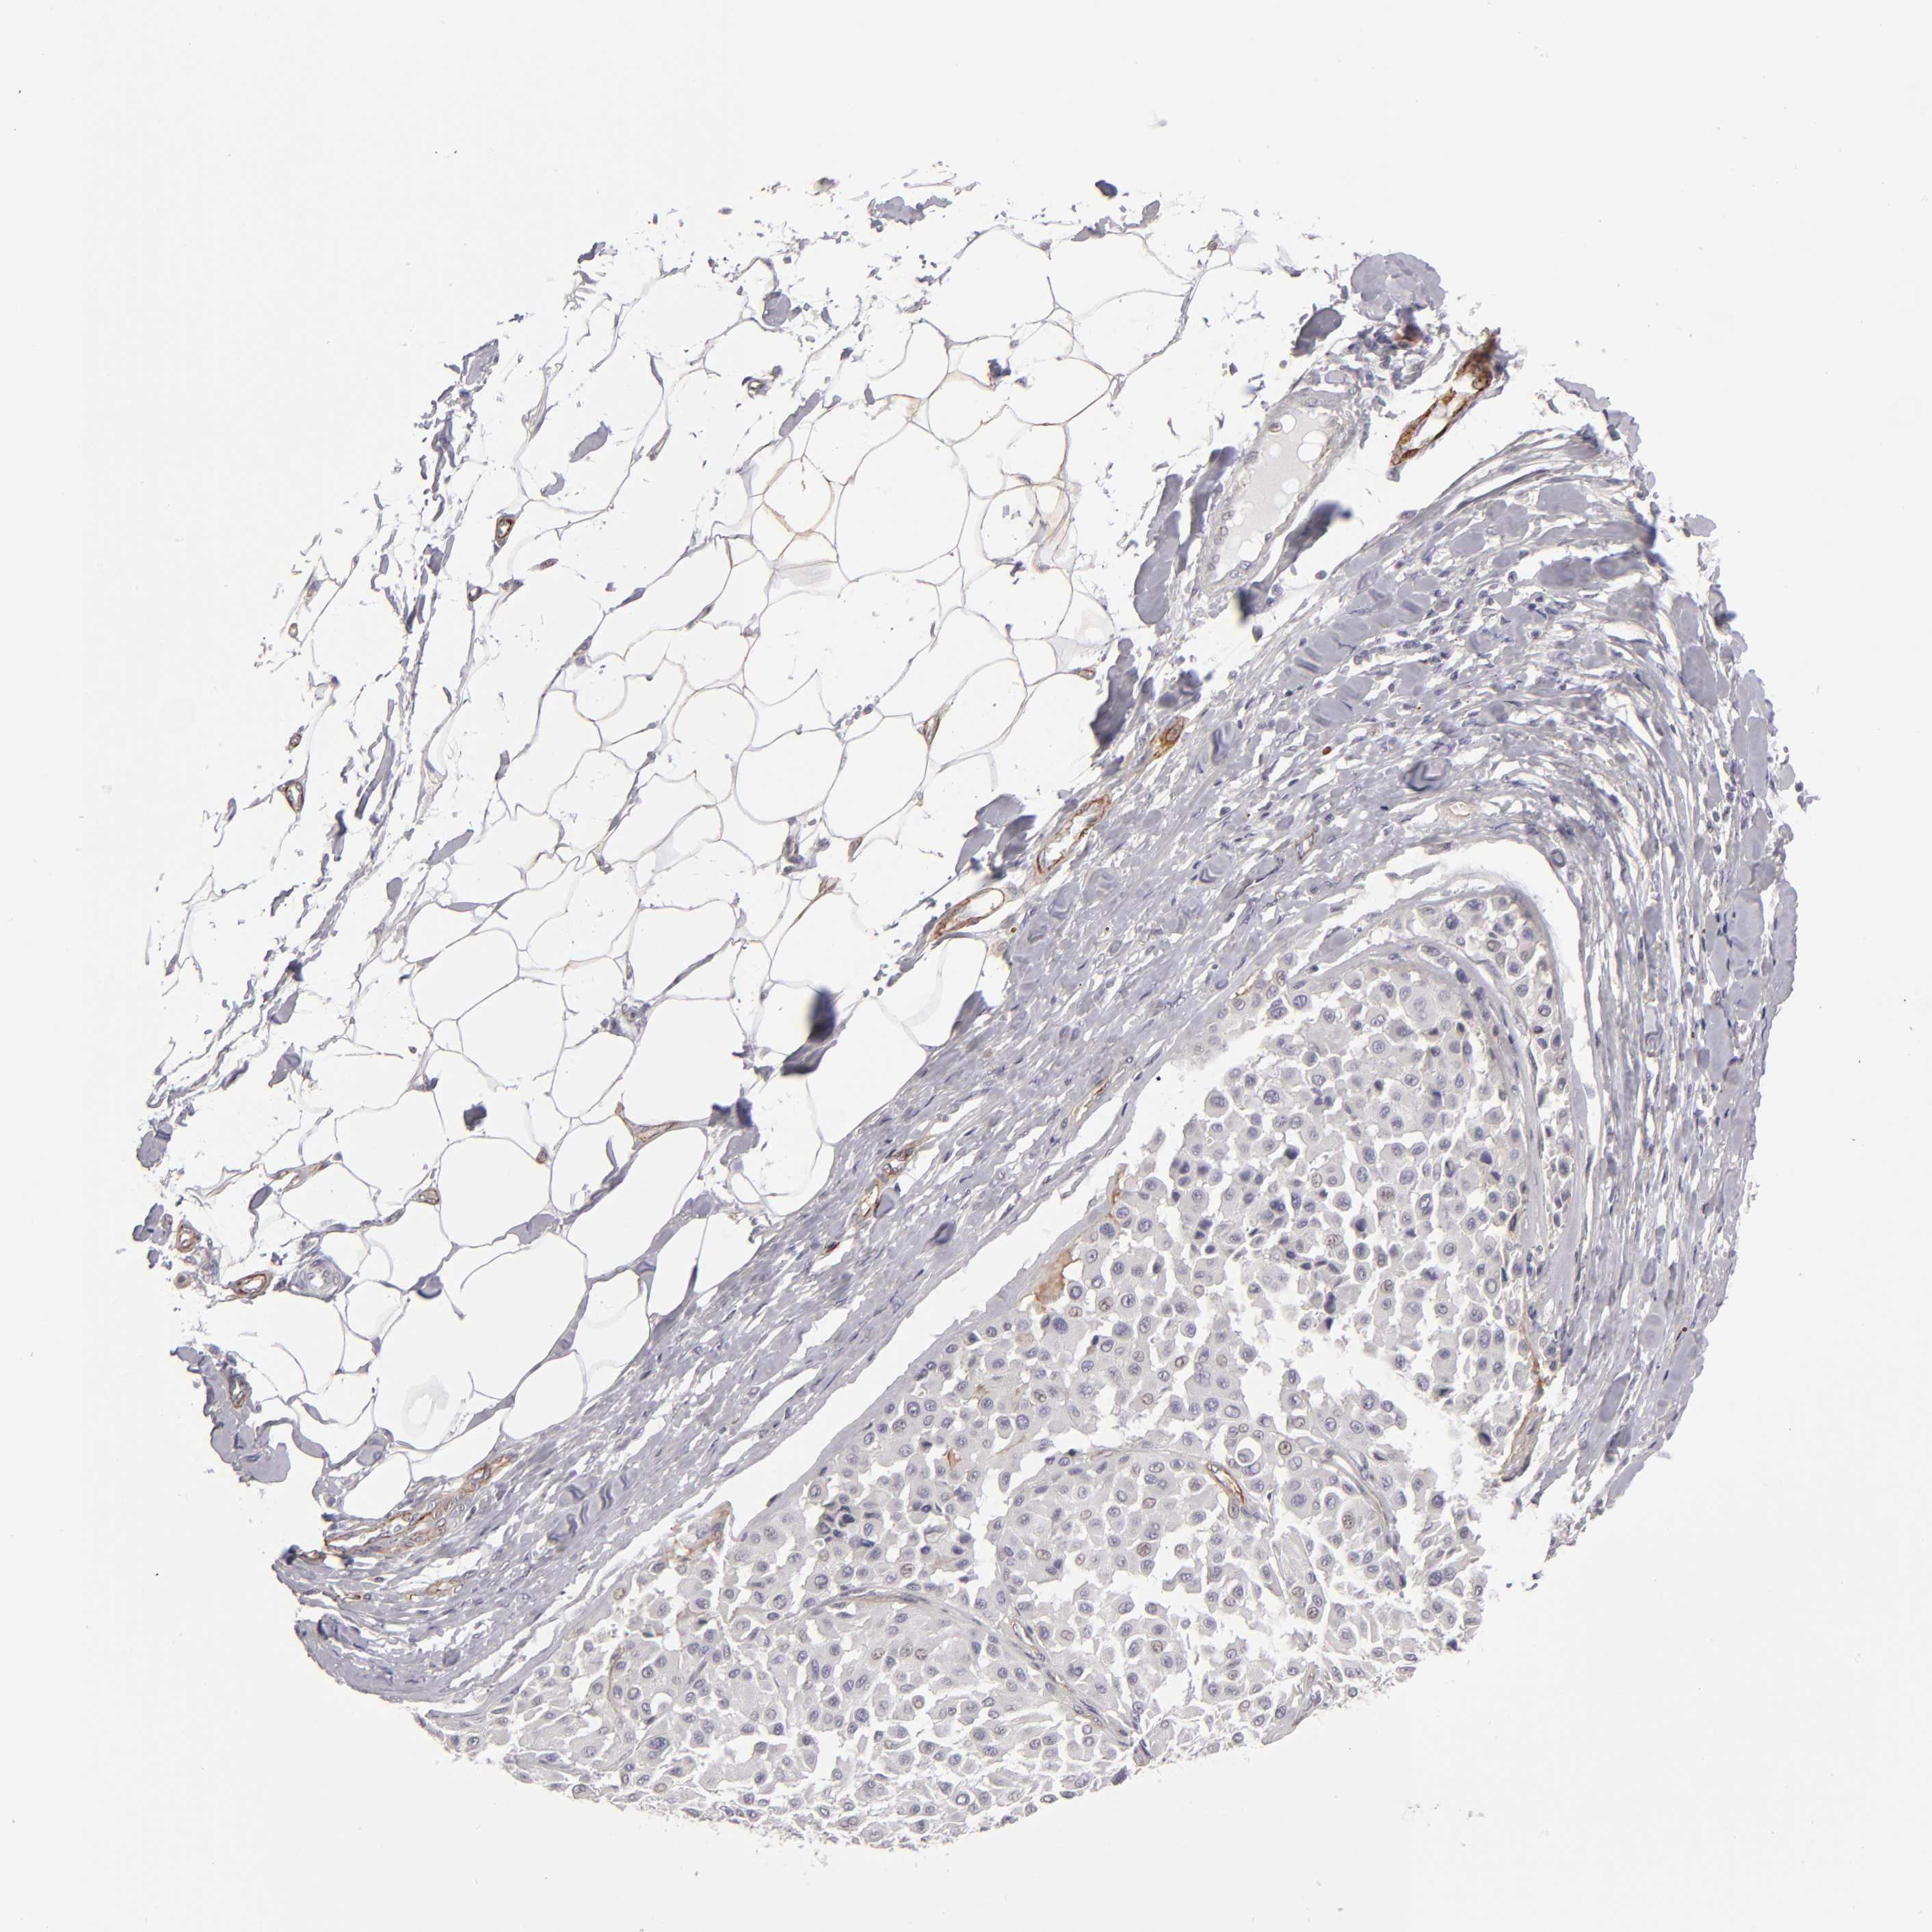

MELANOMA - Protein expressioni

A mouse-over function shows sample information and annotation data. Click on an image to view it in a full screen mode. Samples can be filtered based on level of antibody staining by selecting one or several of the following categories: high, medium, low and not detected. The assay and annotation is described here.

Note that samples used for immunohistochemistry by the Human Protein Atlas do not correspond to samples in the TCGA dataset.

Antibody stainingi

Antibody staining in the annotated cell types in the current human tissue is reported as not detected, low, medium, or high, based on conventional immunohistochemistry profiling in selected tissues. This score is based on the combination of the staining intensity and fraction of stained cells.

Each image is clickable and will lead to virtual microscopy that enables deeper exploration of all samples and also displays staining intensity scores, fraction scores and subcellular localization as well as patient and tissue information for each sample.

Antibody HPA002717

Staining

High

Medium

Low

Not detected

Intensity

Strong

Moderate

Weak

Negative

Quantity

>75%

75%-25%

<25%

None

Location

Nuclear

Cytoplasmic/membranous

Cytoplasmic/membranous,nuclear

Malignant melanoma, NOS

Malignant melanoma, Metastatic site